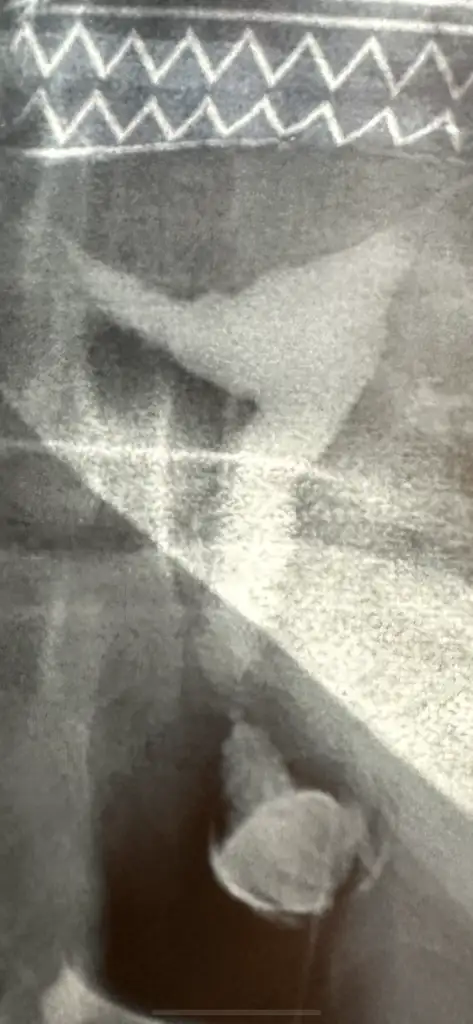

Merhaba ben mayıs ayı sonunda tüp bebek e başlıcm rahim filmi istedi doktor sağ tarafa dogru girinti çıktı şekil bozukluğu sıkıntı mı hamilelik için

Eklentiler

• A5184320-AC79-4928-978E-72832A1F7C91.webp

A5184320-AC79-4928-978E-72832A1F7C91.webp

24,8 KB · Görüntüleme: 50